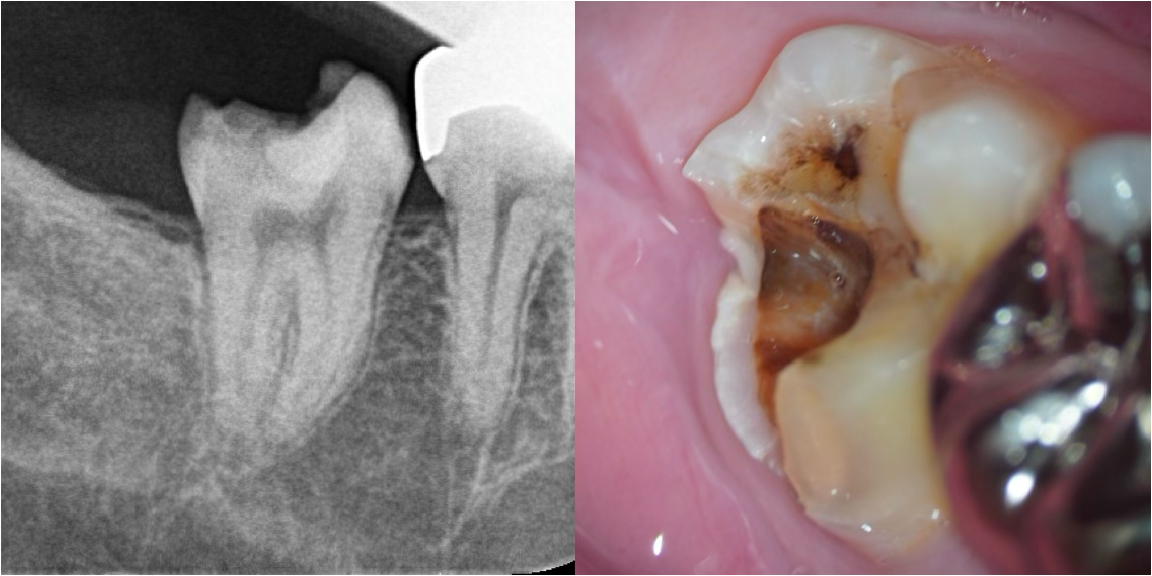

通常のレントゲン写真では根の先の状態は不明瞭でした。おそらく、前医では、神経の検査を的確に行うことが難しかったことと、レントゲンでは根の先の状態の判断に迷ったため、患歯(どの歯が原因か)が断定できなかったと推測されます。

CTを撮影したところ、根の先にはっきりと黒い影(膿・骨の吸収像)が認められ、臨床検査、レントゲン検査から、左上の前歯が原因と確定しました。

根の中への細菌感染の経路は、おそらく古い詰め物の隙間から虫歯が進行し、そこから歯の内部へ感染が進んだものと推測されました。